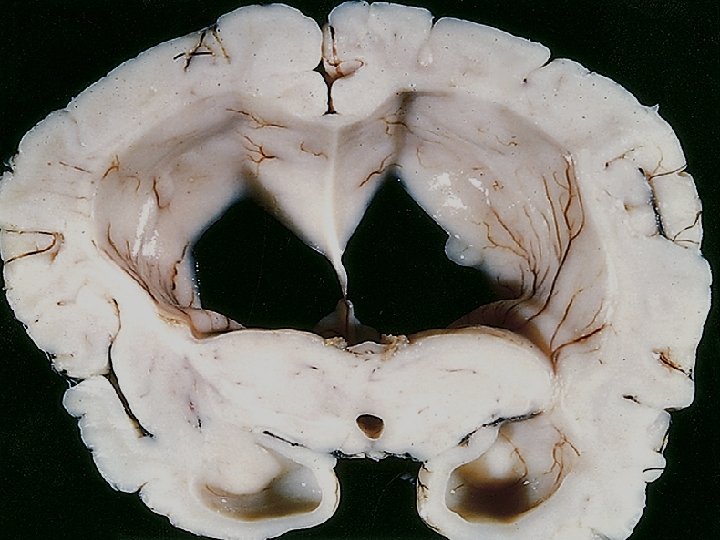

• • Hydrocephalus refers to the accumulation of excessive CSF within the ventricular system Most cases occur as a consequence of impaired flow or impaired resorption of CSF In rare instances (e. g. , tumors of the choroid plexus), overproduction of CSF may be responsible When hydrocephalus develops in infancy before closure of the cranial sutures, there is enlargement of the head

Hydrocephalus developing after fusion of the sutures, in contrast, is associated with expansion of the ventricles and increased intracranial pressure, without a change in head circumference If there is an obstacle to the flow of CSF within the ventricular system, then a portion of the ventricles enlarges while the remainder does not. This pattern is referred to as noncommunicating hydrocephalus and is most commonly seen with masses at the formamen of Monro or aqueduct of Sylvius In communicating hydrocephalus all of the ventricular system is enlarged; here the cause is most often reduced reabsorption of CSF

Abnormal buildup of cerebrospinal fluid (CSF) in the ventricles of the brain It can result from congenital and acquired etiologies. The fluid is often under increased pressure (but not always) and can compress and damage the brain.